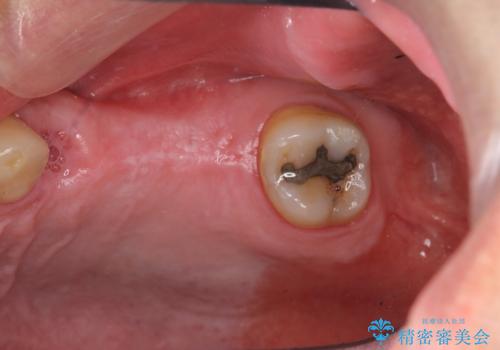

- 長期間放置してしまった虫歯の治療を希望され来院されました。

・重度虫歯による残根状態・欠損歯→インプラント補綴

今回、左下6は頬側歯頚部に虫歯があり圧下を行ったことからクラウンにより補綴を行いました。